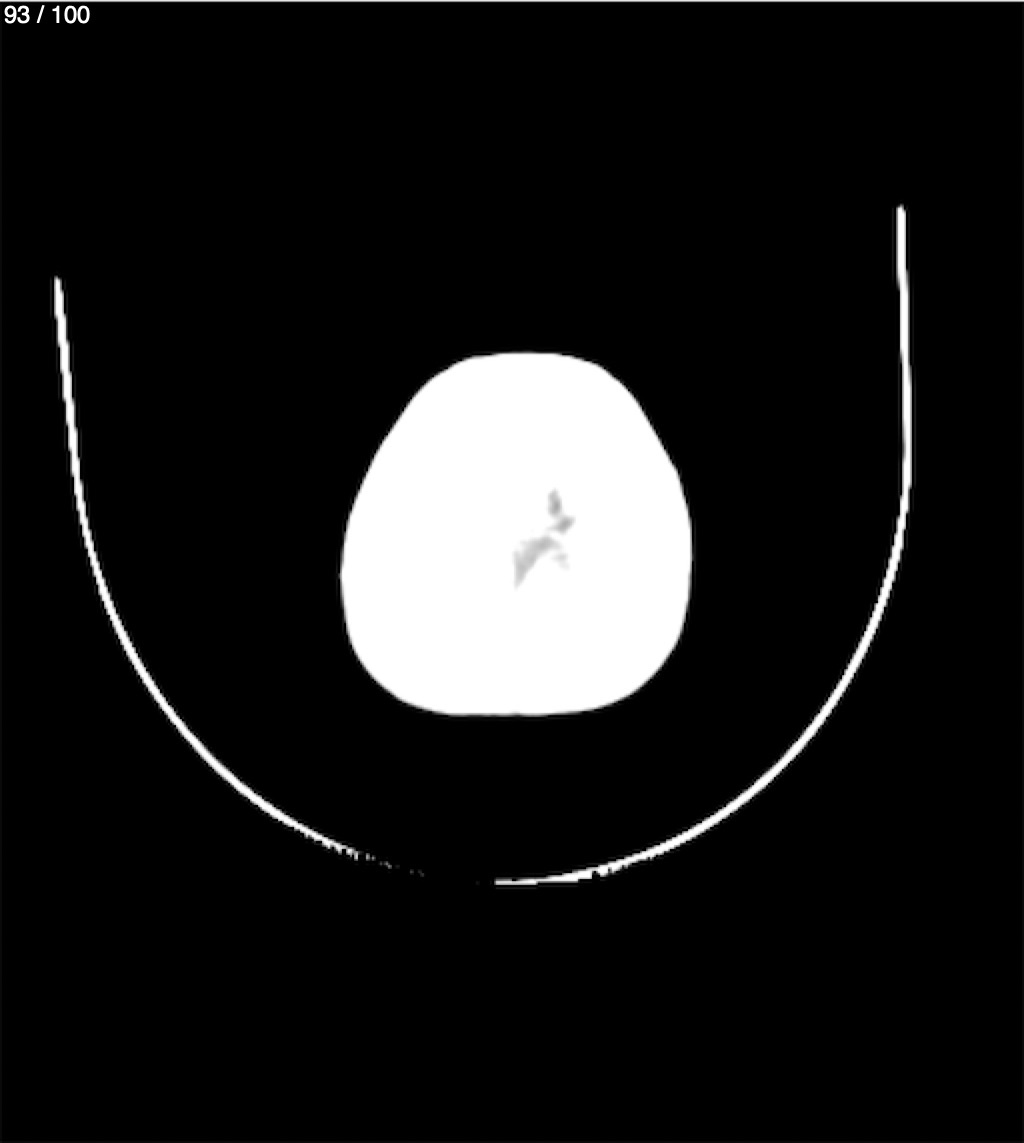

Catarino Perez Escobar 85A - T.C Craneo